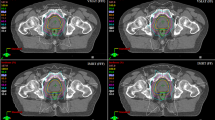

For each patient, six plans were generated, and the results were then divided into two sets. The first result set was VMAT at different MICs (MLCi2, Agility (FFF), and Agility (FF)), while the second set included corresponding IMRT results. The acceptance criteria achieved in all plans with VMAT and IMRT techniques depend on the PTVs and OARs. Figure 1A, B show the dose distribution for VMAT and IMRT plans with different MLC designs for PTV60 and PTV44. Also, Fig. 2A, B reveal the PTV60 DVH of VMAT and IMRT with different MLC. Additionally, Tables 2, 3 summarize the dosimetric DVH parameters of the PTVs and OARs with different MLC types for VMAT plans.